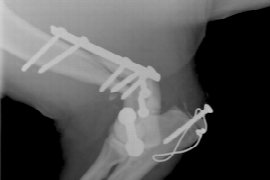

Alasdair is an internationally recognised orthopaedic specialist and is currently the only specific orthopaedic specialist in registered Victoria. He worked for 11 years in general practice followed by spending the last 11 years in specialist orthopaedic practice. As well as his clinical duties he regularly lectures nationally and internationally and is an honorary lecturer for the University of Liverpool. Prior to moving with his family and joining the Veterinary Referral Hospital (VRH) -Hallam in January 2018, he spent the previous 7 years in one of the busiest orthopaedic referral clinics in the UK. This clinic had a large case load of high performance working dogs and competition agility dogs, as well as plenty of pet dogs, with many of these dogs sustaining fractures. He has a wealth of experience in returning these dogs to function and has continued to enjoy fracture fixation at VRH.